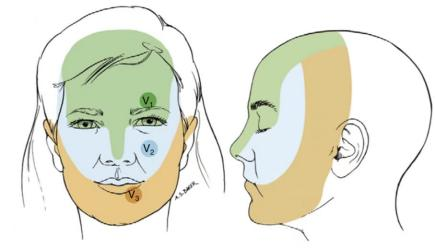

近日我院疼痛科成功开展一例经皮三叉神经半月节球囊压迫术,为一位82岁高龄患者治疗困扰多年的三叉神经痛。患者受三叉神经痛折磨2年多,院外经药物等治疗疼痛控制差,吃东西、说话、刷牙疼痛严重,严重影响日常生活和睡眠,来到我院疼痛科。完善相关检查后,诊断原发性三叉神经痛,累及右侧第2、3支,经过疼痛科专家们研讨,决定行经皮三叉神经半月节球囊压迫术,手术时间10多分钟,术后患者疼痛立刻缓解,3天后顺利出院。

三叉神经痛又称“天下第一痛”,主要以单侧头面部反复发作、短暂性、电击样、烧灼样、刀割样等疼痛为特点,突发突止,一般历时几秒到数分钟,通常说话、咀嚼、洗脸、刷牙、吹风等时可诱发,常常累及三叉神经一个或多个分支。严重影响患者生活质量。具体病因目前不清楚,考虑:1.和神经伴行动脉血管关系太近,动脉搏动刺激神经,诱发疼痛。2.考虑神经自身病变引起。

经过面部口角处穿刺到三叉神经半月节内,放入球囊,向球囊里打入对比剂,使球囊扩张,完美显示一个“梨”形,压迫3-5分钟,压迫毁损感觉神经,保留运动神经,阻断疼痛信号传导,达到止痛目的。适合单支或多支发病患者,尤其高龄、合并症多,不愿意接受开颅手术患者。术后面部稍有麻木。

适合第II、III支单支发病患者。